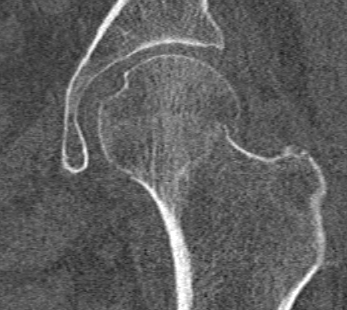

Pauwel's Classification

Based on vertical orientation of fracture line

- increased verticality / increased shear

- increased risk of noonunion / AVN

Type I: < 30° from horizontal

Type II: 30 - 50° from horizontal

Type III: > 50° from horizontal

Pauwel's type III